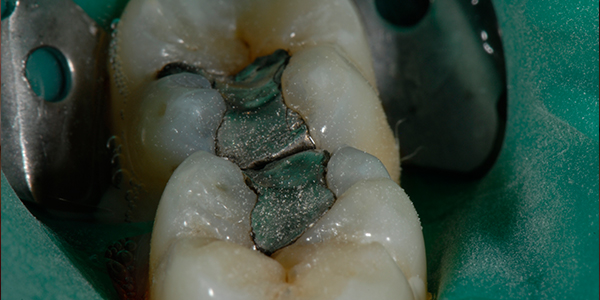

Before

Silver Filling Replacement